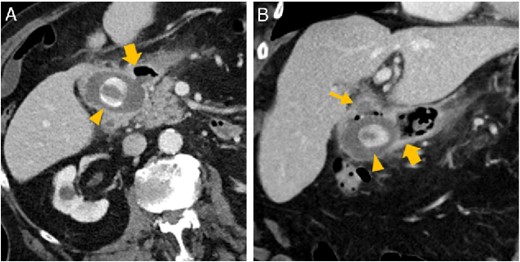

Abdominal CT in axial (A) and oblique parasagittal reconstruction (B); gallstone in the duodenal bulb (arrowhead

), pylorus (thick arrow

), chronically inflamed, and collapsed gall bladder with fistula to the duodenum (thin arrow

); image courtesy of Helmut Schöllnast, State Hospital Graz II, Austria.